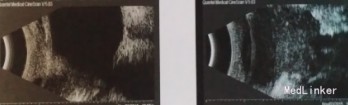

体征:双眼闭合可,眼球各方向运动正常,右眼下睑未见红肿,睑缘位置正常,可扪及质韧边界不清肿物,大小约1cm*0.5cm,左眼下睑肿胀,可扪及大小约2cm*1cm大小肿物,质硬,边界清,活动度一般,无压痛,无皮温升高。双眼角膜清亮,前房深浅正常,房闪阴性,瞳孔直径3mm,光反灵敏,晶体清亮,眼底视乳头色淡红界清,杯盘比0.3,视网膜平伏,黄斑中反清。 辅助检查:双眼B超于眼眶内下方可见约9.2*6.3mm,22.9*21.1mm低回声光团,边界清,形态不规则,内光点分布不均匀。MRI双眼下睑见不规则形软组织肿物,并累及球下肌外间隙,左眼下睑明显,境界尚清,最大横径大小分别为1.9*2.3cm,0.7*1.4cm,T1为等信号,T2及压脂序列为稍高信号,增强扫描中度强化。考虑炎性假瘤。